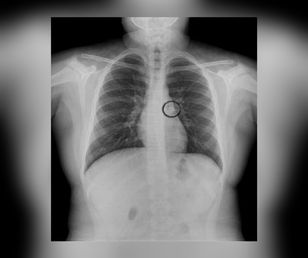

Dziewczynce wypadł ząb. Przez sen wciągnęła go do oskrzeli